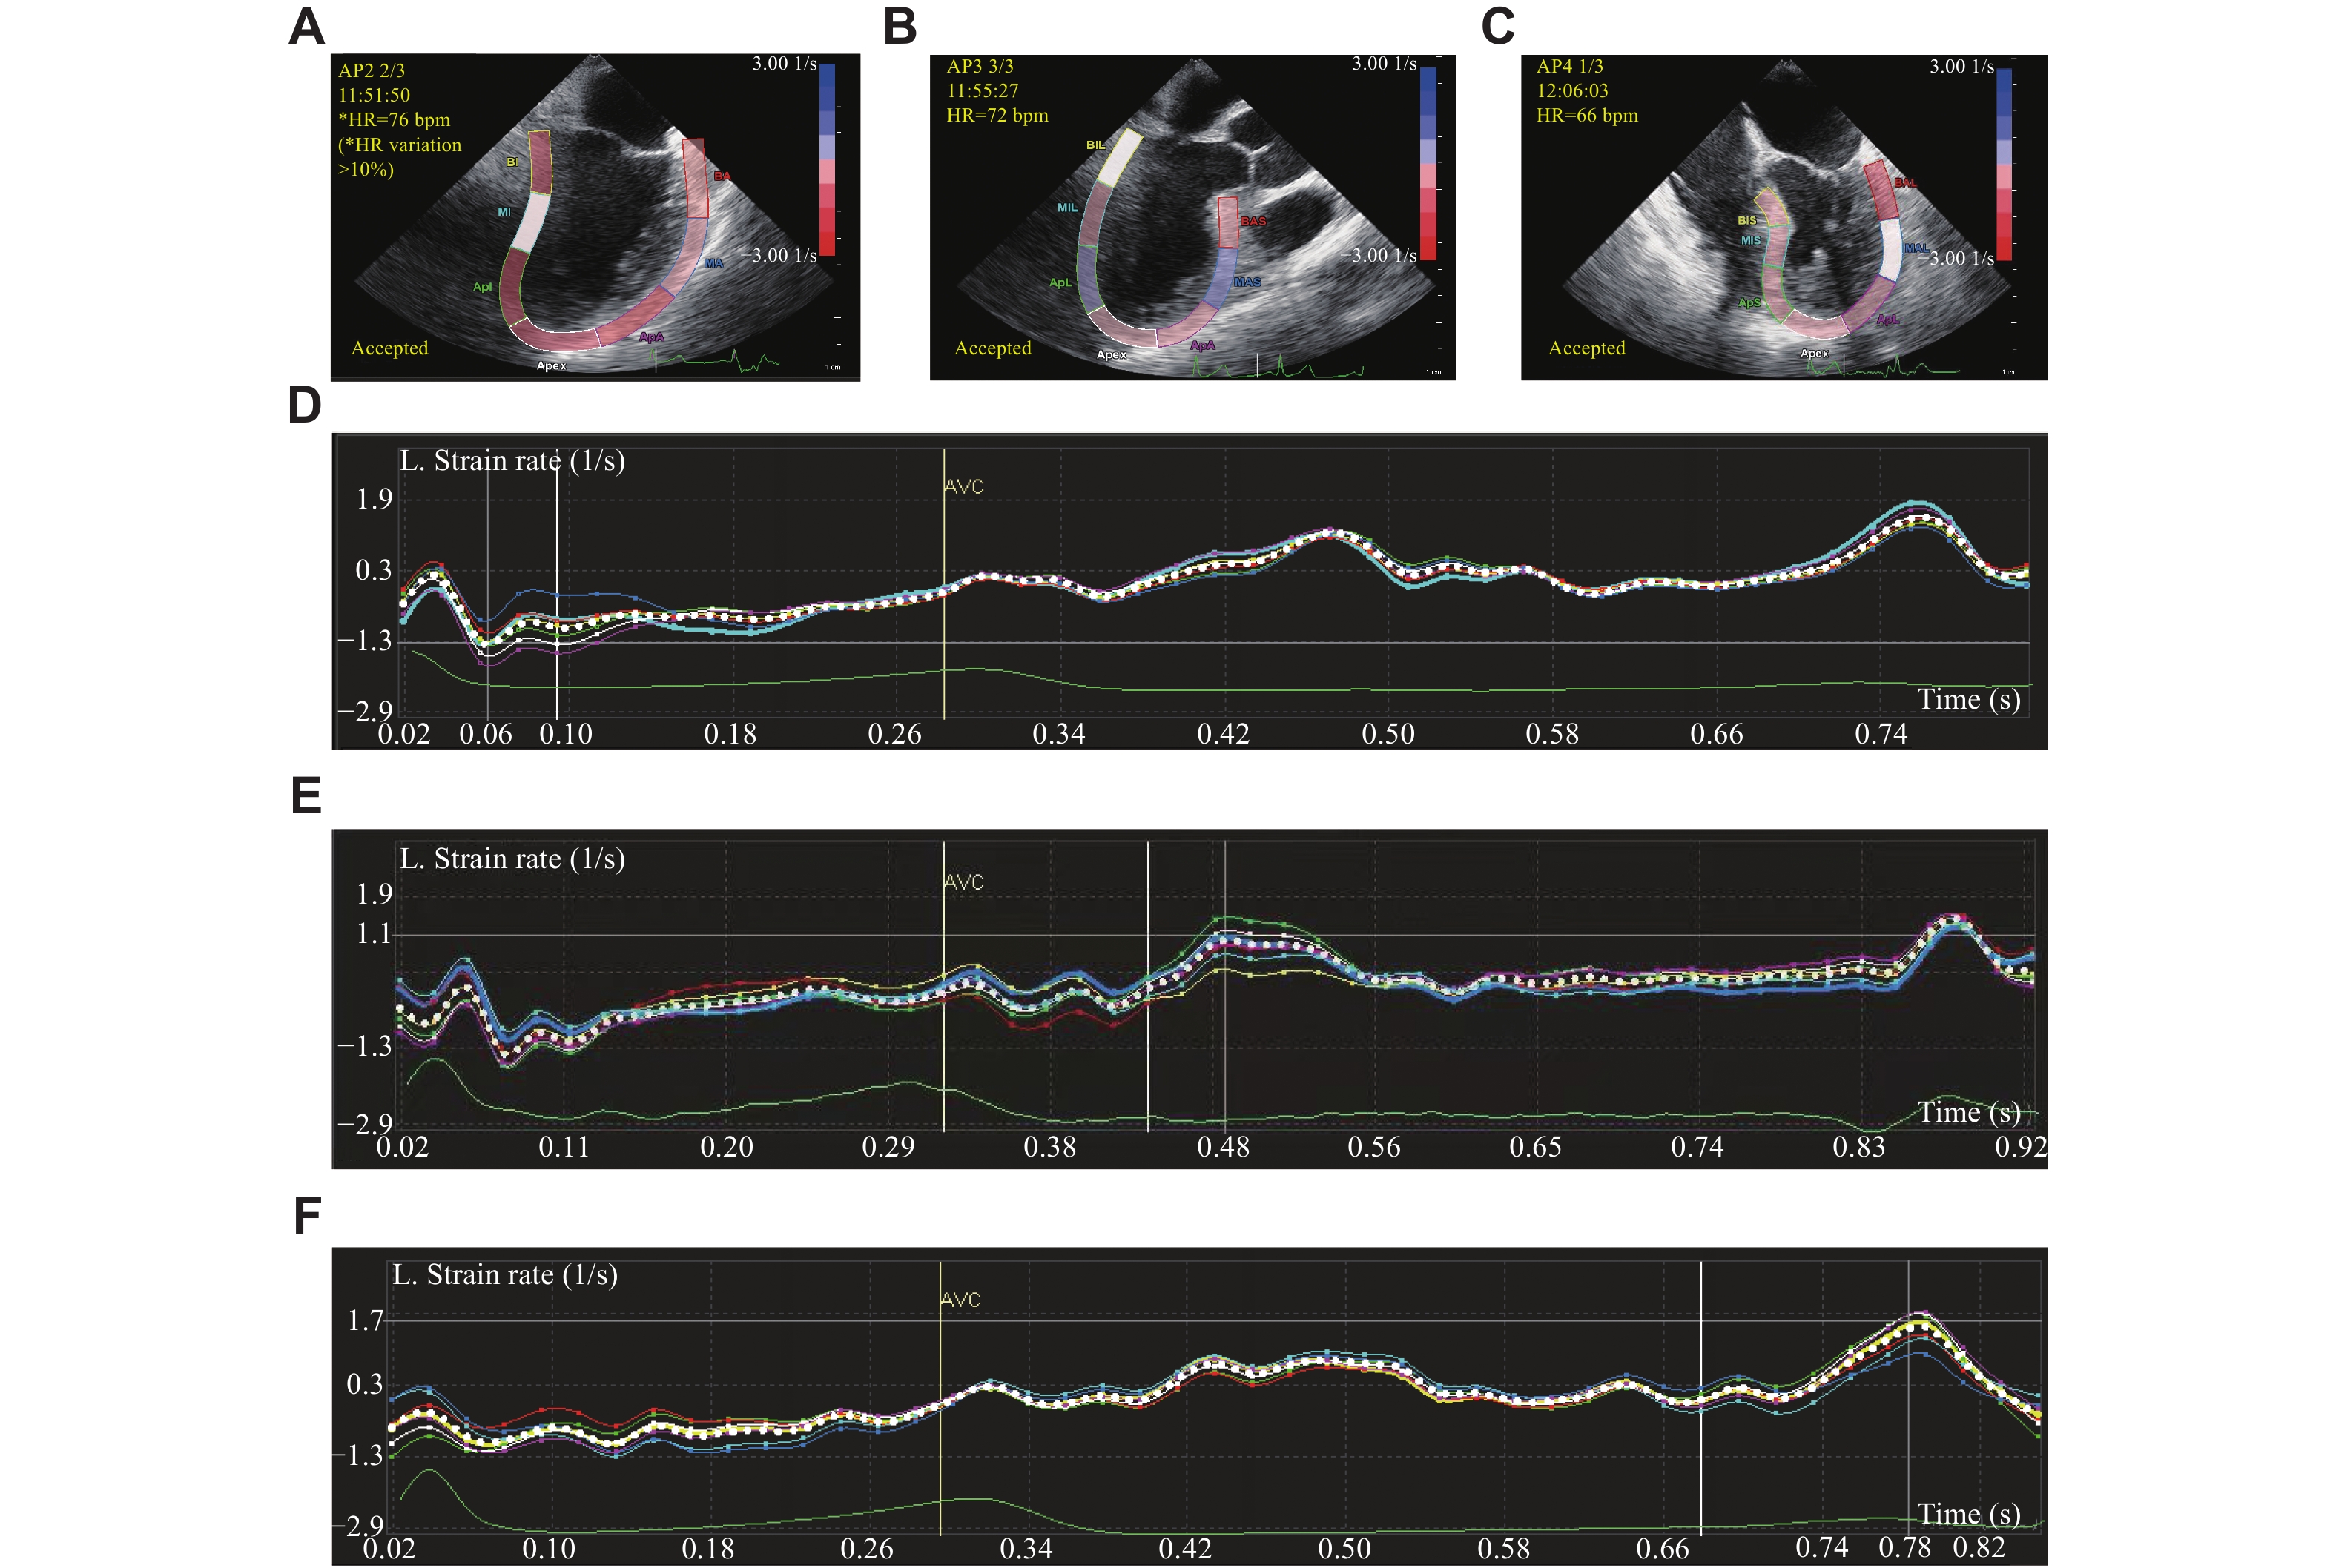

• The present study aimed to dynamically observe the segmental and global myocardial movements of the left ventricle during coronary artery bypass grafting by transesophageal speckle-tracking echocardiography, and to assess the effect of sevoflurane on cardiac function. Sixty-four patients scheduled for the off-pump coronary artery bypass grafting were randomly divided into a sevoflurane-based anesthesia (AS) group and a propofol-based total intravenous anesthesia (AA) group. The AS group demonstrated a higher absolute value of left ventricular global longitudinal strain than that of the AA group at both T1 (after harvesting all grafts and before coronary anastomosis) and T2 (30 min after completing all coronary anastomoses) (P < 0.05). Moreover, strain improvement in the segment with the highest preoperative strain was significantly reduced in the AS group, compared with the AA group at both T1 and T2 (P < 0.01). The flow of the left internal mammary artery-left anterior descending artery graft was superior, and the postoperative concentration of troponin T decreased rapidly in the AS group, compared with the AA group (P < 0.05). Compared with total intravenous anesthesia, sevoflurane resulted in a significantly higher global longitudinal strain, stroke volume, and cardiac output. Sevoflurane also led to an amelioration in the condition of the arterial graft. Furthermore, sevoflurane significantly reduced strain improvement in the segmental myocardium with a high preoperative strain value. The findings need to be replicated in larger studies.